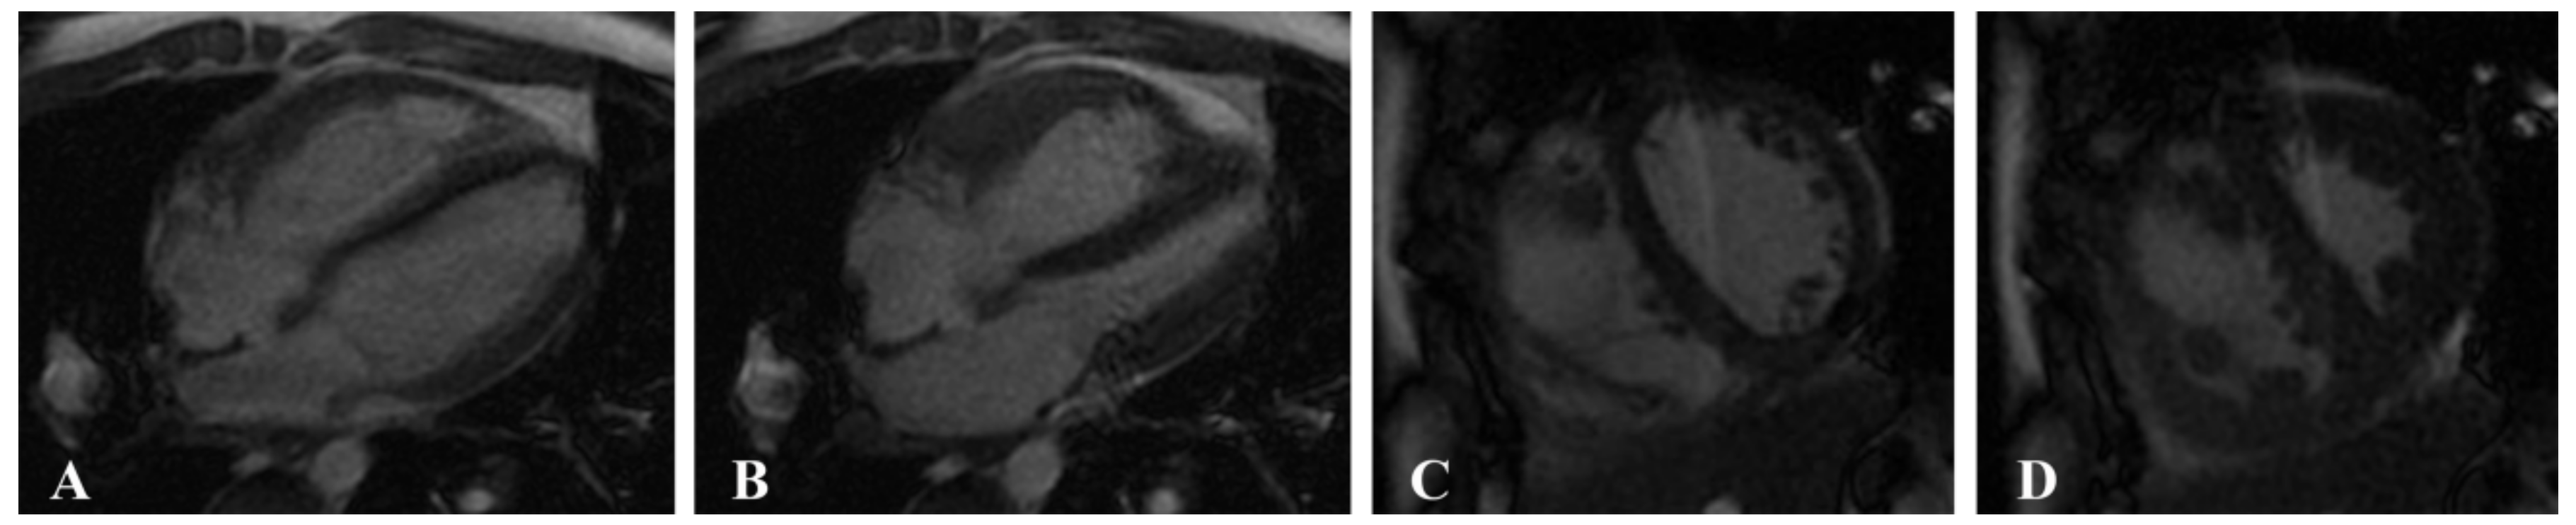

2.2. MRI Acquisition

2.3. Image Postprocessing

2.3.1. Cardiac Function Parameters

2.3.2. Myocardial Strain Parameters